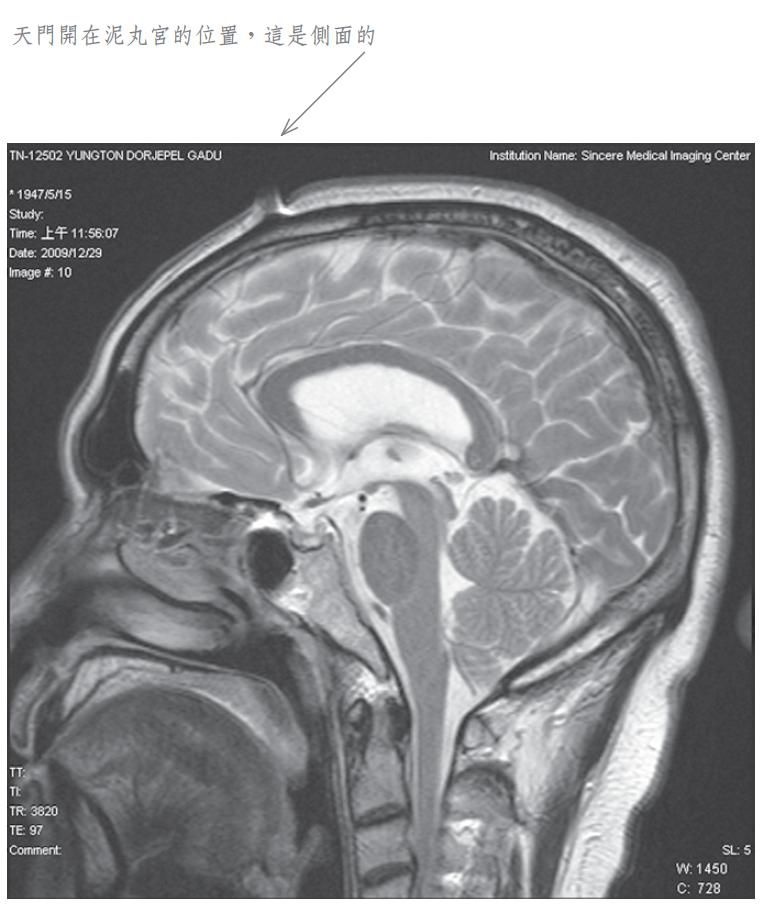

當我將此種修法中發生之覺受稟報佛陀師父時,佛陀師父又為我傳了秘密口訣。經過一段時日,佛陀師父在公開開示的法音帶中,才提到我曾經修法達到化身境的初級,即是素化身的意思。為了讓眾生明瞭佛法的偉大,事隔多年之後,我特別於二零零九年十二月廿九日,到中心綜合醫院安排磁振造影(MRI)頭部的攝影檢查,結果發現泥丸宮的部位出現一個1.5公分寬深的開口,同時拍下了有一股神識出氣衝出頭部的實況。負責檢查的醫生非常驚訝稱奇,但無法解釋其原因,因而將它歸因於非人之所為。我其實非常清楚,我的神識化身本來就是從這裡出入的,以下是在醫院MRI檢查的掃瞄片。